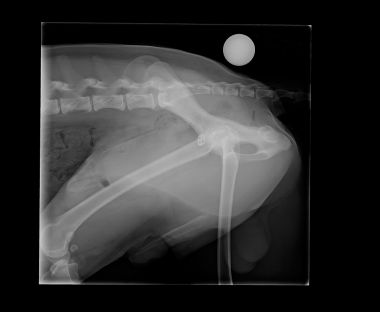

Voici les radios du 23 octobre... la tête du fémur est nécrosée...sur problème infectieux... je ne suis pas contente... la seule alternative qu'il reste maintenant et de tout enlever, de couper la tête du fémur... et Twarak devra vivre ainsi.

Il me dise que pour un chien comme lui, c'est très gérable... je suis triste pour Twarak....

opération et mise en place d'un bouton-clou dans la tête du fémur gauche